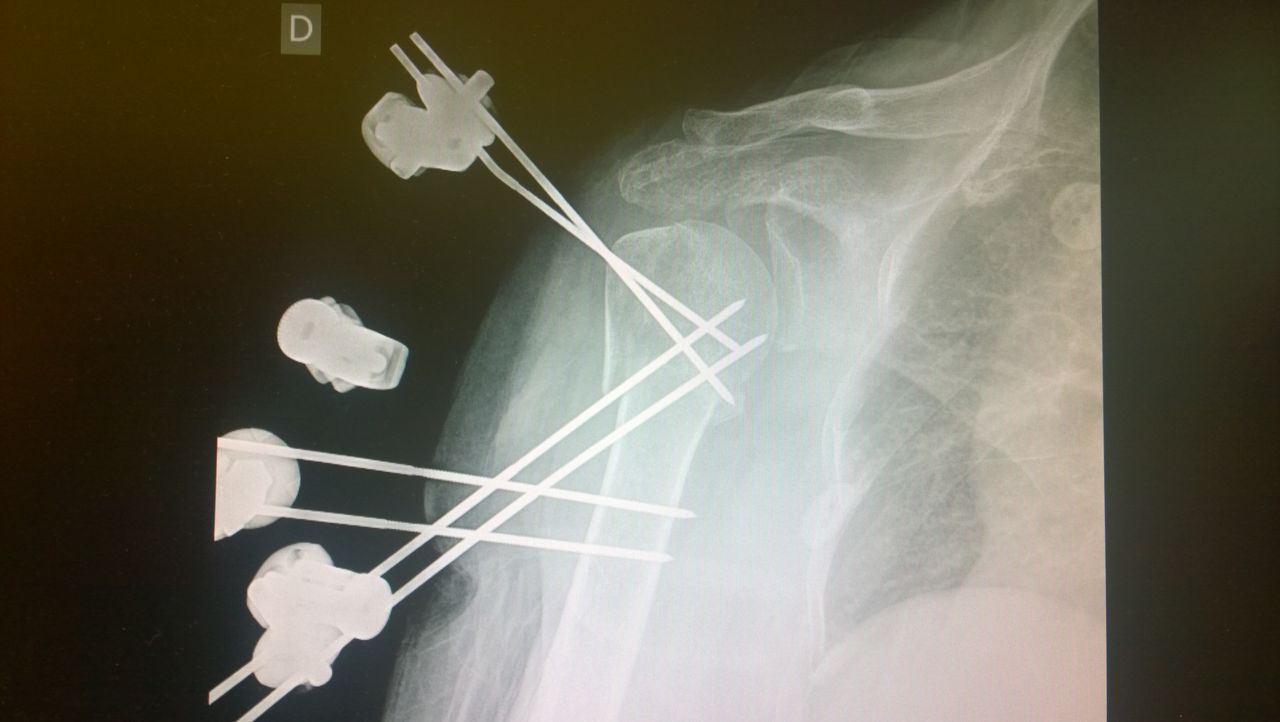

Specialista di chirurgia della Spalla, del Gomito e di traumatologia dello sport. Opinion leader e docente di fama Europea della patologia dell'arto superiore, con particolare interesse verso le ricostruzioni legamentose, l'artroscopia, la sostituzione protesica ed interventi di revisione. Gran parte della mia pratica clinica e chirurgica è attualmente il trattamento di fallimenti di altri interventi o traumi non guariti correttamente e il trattamento dell'atleta ad alto livello con patologie di spalla e gomito.

Parallelamente all'attività chirurgica di revisione ho da sempre approfondito la chirurgia mini invasiva dell'arto superiore, soprattutto sviluppando techniche chirurgiche come l'artroscopia di gomito e la fissazione esterna per le fratture di omero prossimale.

Most of my surgical practice is currently the treatment of failures of prior surgeries and post traumatic deformities. I'm also greatly involved in the treatment of high level athletes and I developed my skills in mini-invasive surgeries, especially elbow arthroscopy and mini-invasive techniques for the treatment of proximal humeral fractures.